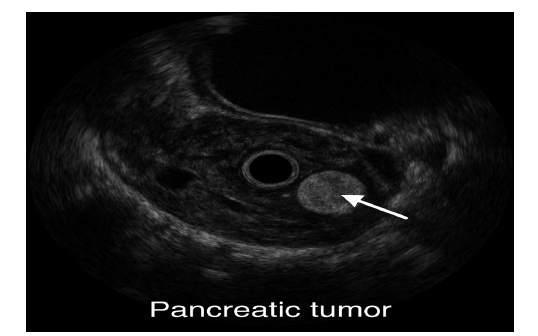

Ultrasound, especially Endoscopic Ultrasound (EUS) provides high-resolution images and allows fine-needle aspiration (FNA) to obtain tissue samples. It is highly sensitive for detecting small tumours and guiding biopsy procedures (Eloubeidi et al., 2004). Figure 6 revealed the Endoscopic ultrasound (EUS) image demonstrating a hypoechoic lesion within the pancreatic parenchyma, consistent with a suspected malignant neoplasm. The lesion exhibits irregular margins and heterogeneous echotexture, features commonly associated with pancreatic adenocarcinoma. EUS provides high-resolution imaging and facilitates fine-needle aspiration for histopathological confirmation.

Figure 6:Endoscopic ultrasound imaging of pancreatic cancer. Source: Eloubeidi et al. (2004).